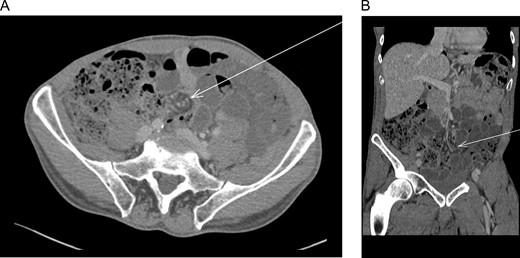

SBO was noted secondary to the cut end V-LOC suture, which had become integrated into the small bowel mesenterium creating a volvulus with associated ischemia (Fig. 2).

(A) Laparoscopic exploration revealed to barbed suture exposed from the peritoneum and wrapped in mesentery. (B) Laparoscopic exploration revealed to small intestine volvulus.